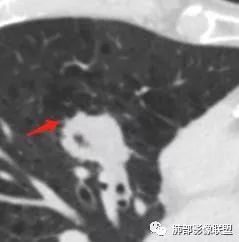

我们的主要目标:中叶内侧段结节 医学百科网 | YxBaike.Com

深分叶,部分边缘膨隆,也有部分平直 医学百科网 | YxBaike.Com

边缘光滑

部分边缘有短毛刺

我需要看这个是不是近端支气管堵塞,如果近端支气管明确,我就高度怀疑癌 医学百科网 | YxBaike.Com

空泡征 医学百科网 | YxBaike.Com